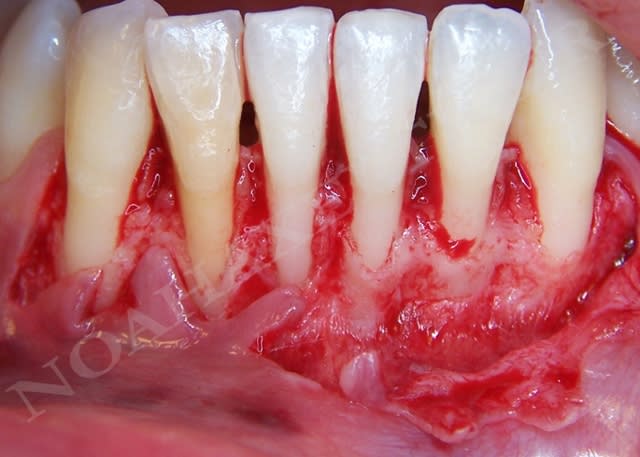

Initial t897lc - Eugenol

Greffon yoownt - Eugenol

Retrait point jgklna - Eugenol

Lit receveur bf5bsr - Eugenol

Sutures gnghlo - Eugenol

noahaxeltiger-olivier

04/02/2009 à 23h18

désolé mes les photos du cas clinique que j'ai posté sont arrivées dans le désordre (encore un mystère Eugénol que nos modos se sont promis de fixer .... il y de cela bien 2-3 mois maintenant ;-))) )

Je ne doute pas une seconde que vous serez les remettre dans le bon ordre chronologique.